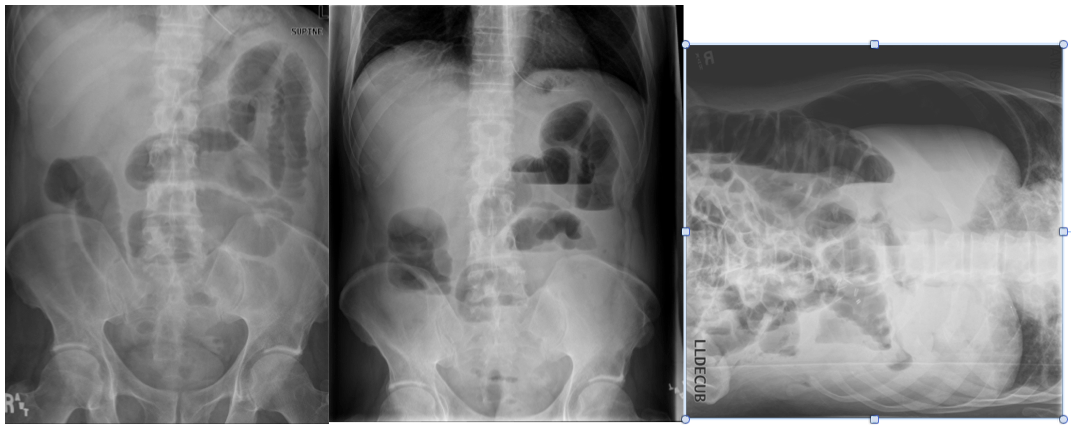

What are the indications for obtaining a KUB?

How is it obtained?

Abdominal pain

supine + upright (if a patient can’t stand upright, then get a lateral decubitus instead)

obtained on an empty stomach (if bowel is filled with fluid, then it won’t show up on the radiograph)